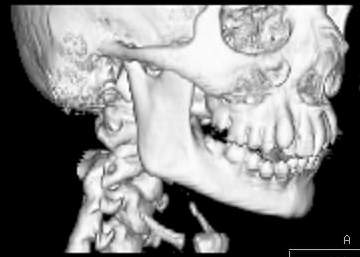

Пациент В., 13 лет. Диагноз: Костный анкилоз левого височно-нижнечелюстного сустава (ВНЧС), левосторонняя микрогения. Болеет с 2-х летнего возраста. Возможная причина развития анкилоза – воспалительный процесс (в первые 1,5 года жизни часто болел простудными заболеваниями, травму родители отрицают). В 3 и 5 лет проводилась редрессация – безуспешно.Прилагаются: ортопантомограмма, кадры СКТ с 3Д реконструкцией. Вопросы: определение тактики лечения – вид и сроки реконструктивно-пластической операции (этапов операции), а именно – неоартропластики и устранения микрогении, медикаментозная терапия в до- и послеоперационный период, ортодонтическое лечение.

Возможно проведение традиционной остеотомии с введением дермо-жирового трансплантата в линию остеотомии. Сроки ортодонтического лечения необходимо обсуждать совместно с ортодонтом и планировать начало лечения до и после оперативного вмешательства. Не исключено применение в дальнейшем остеотомии убоальвеолярных отростков с целью коррекции прикуса.